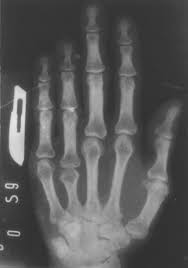

Durante la 2 mitad del siglo 20se han desarrollado mejores métodos para observar el interior del cuerpo humano.Los rayos gamma ponen de manifiesto, ciertos iones radiactivos, que marcan substancias que reaccionan con células cancerosas. La tomografía axial computarizada o tac, utiliza rayos x para producir imágenes tridimensionales de las estructuras corporales.

La resonancia magnética nuclear produce imágenes detalladas sin necesidad de utilizar rayos x, la tomografía de emisión de positrones, permite detectar estados precoces de la enfermedad.

La ecografía utiliza ondas de alta frecuencia para diagnosticar enfermedades y para realizar el seguimiento de embarazos